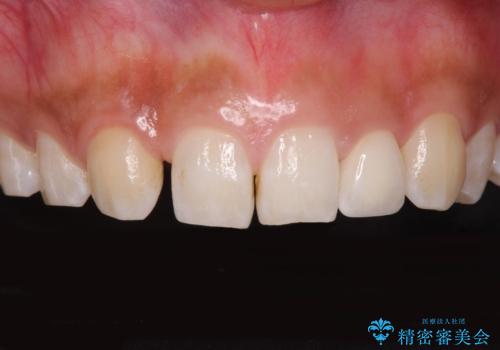

抜歯後そのままブリッジを入れるとブリッジと歯茎の間に大きなすき間ができてしまいます。その結果食べ物がつまりやすくなったり、息もれが生じたりと日常生活に支障をきたしてしまうことがあります。

抜歯後に骨を増やしてあげることで、ブリッジと歯茎との間にすき間が生じにくくなり、適合の良いブリッジを入れることが可能となります。